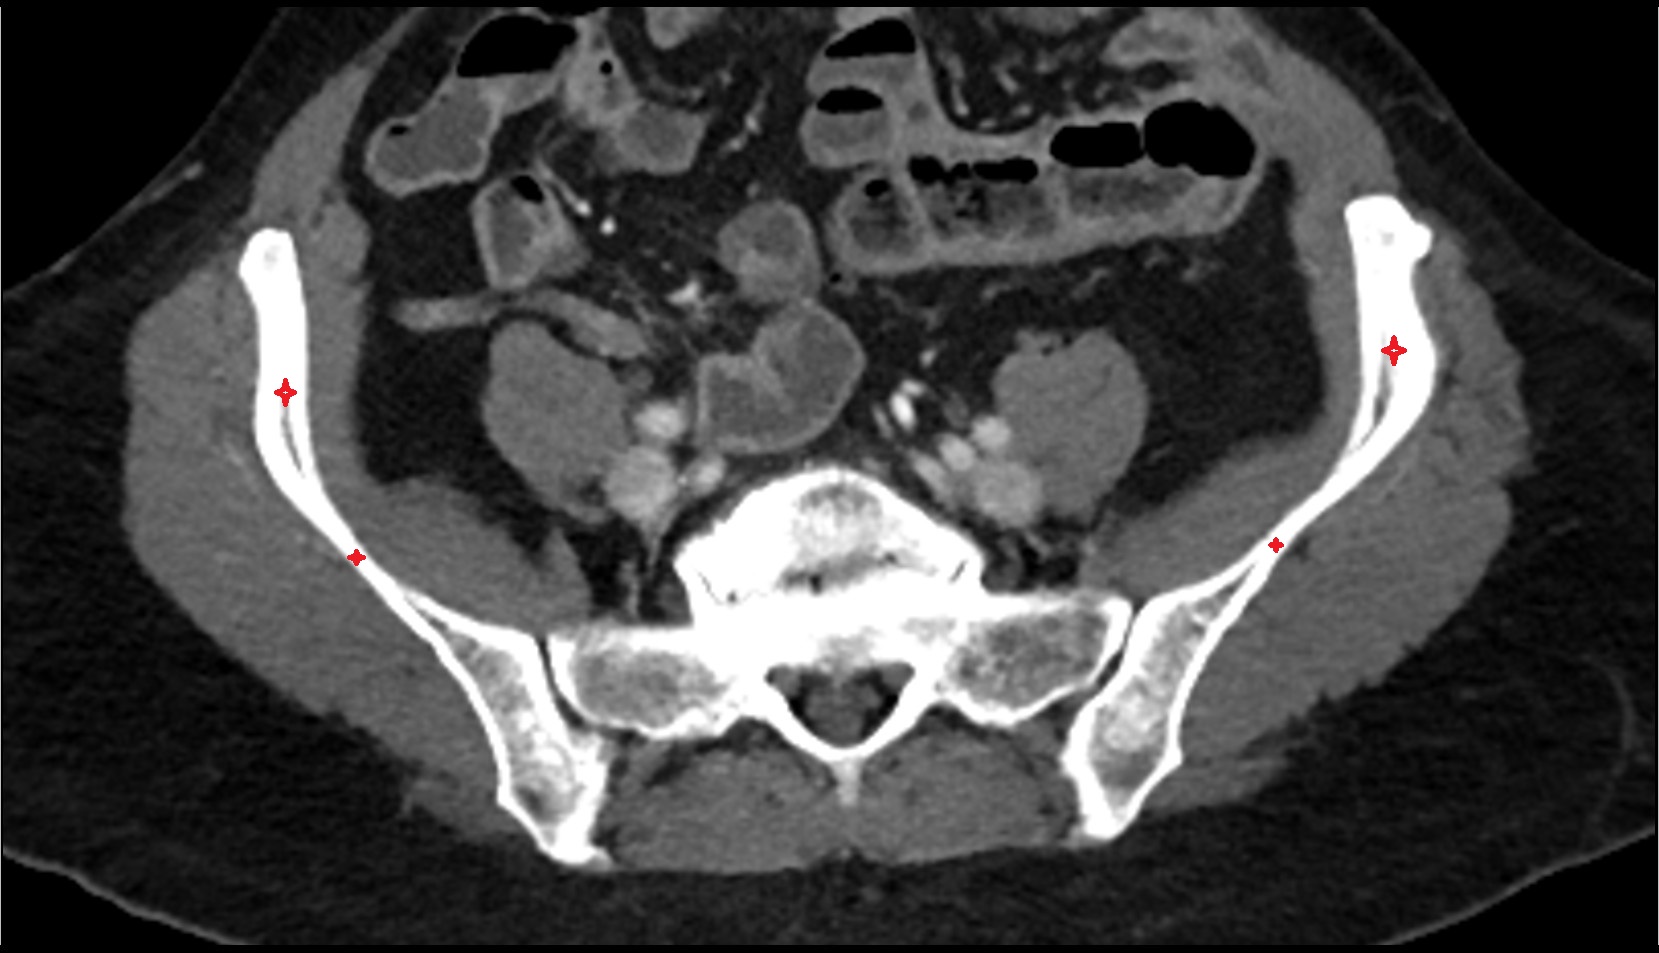

- Ala of ilium (wing of ilium)

- Iliac crest

- Sacroiliac joint

- Deep circumflex iliac artery

- External iliac artery

- External iliac vein